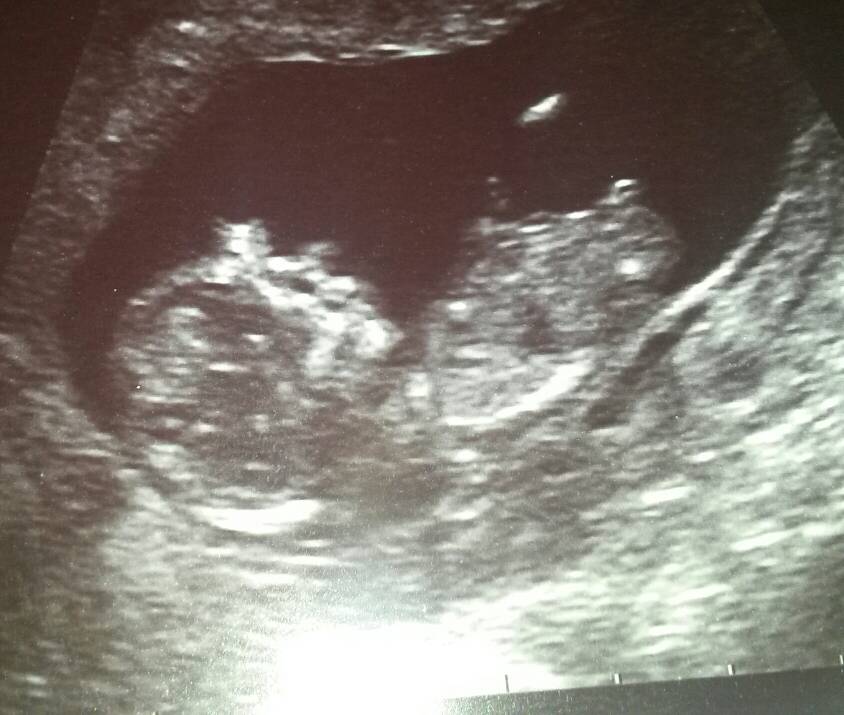

Not sure that's a nub but if it is I'll say boy.

Agree guessing boy

boy

based on skull boy :)